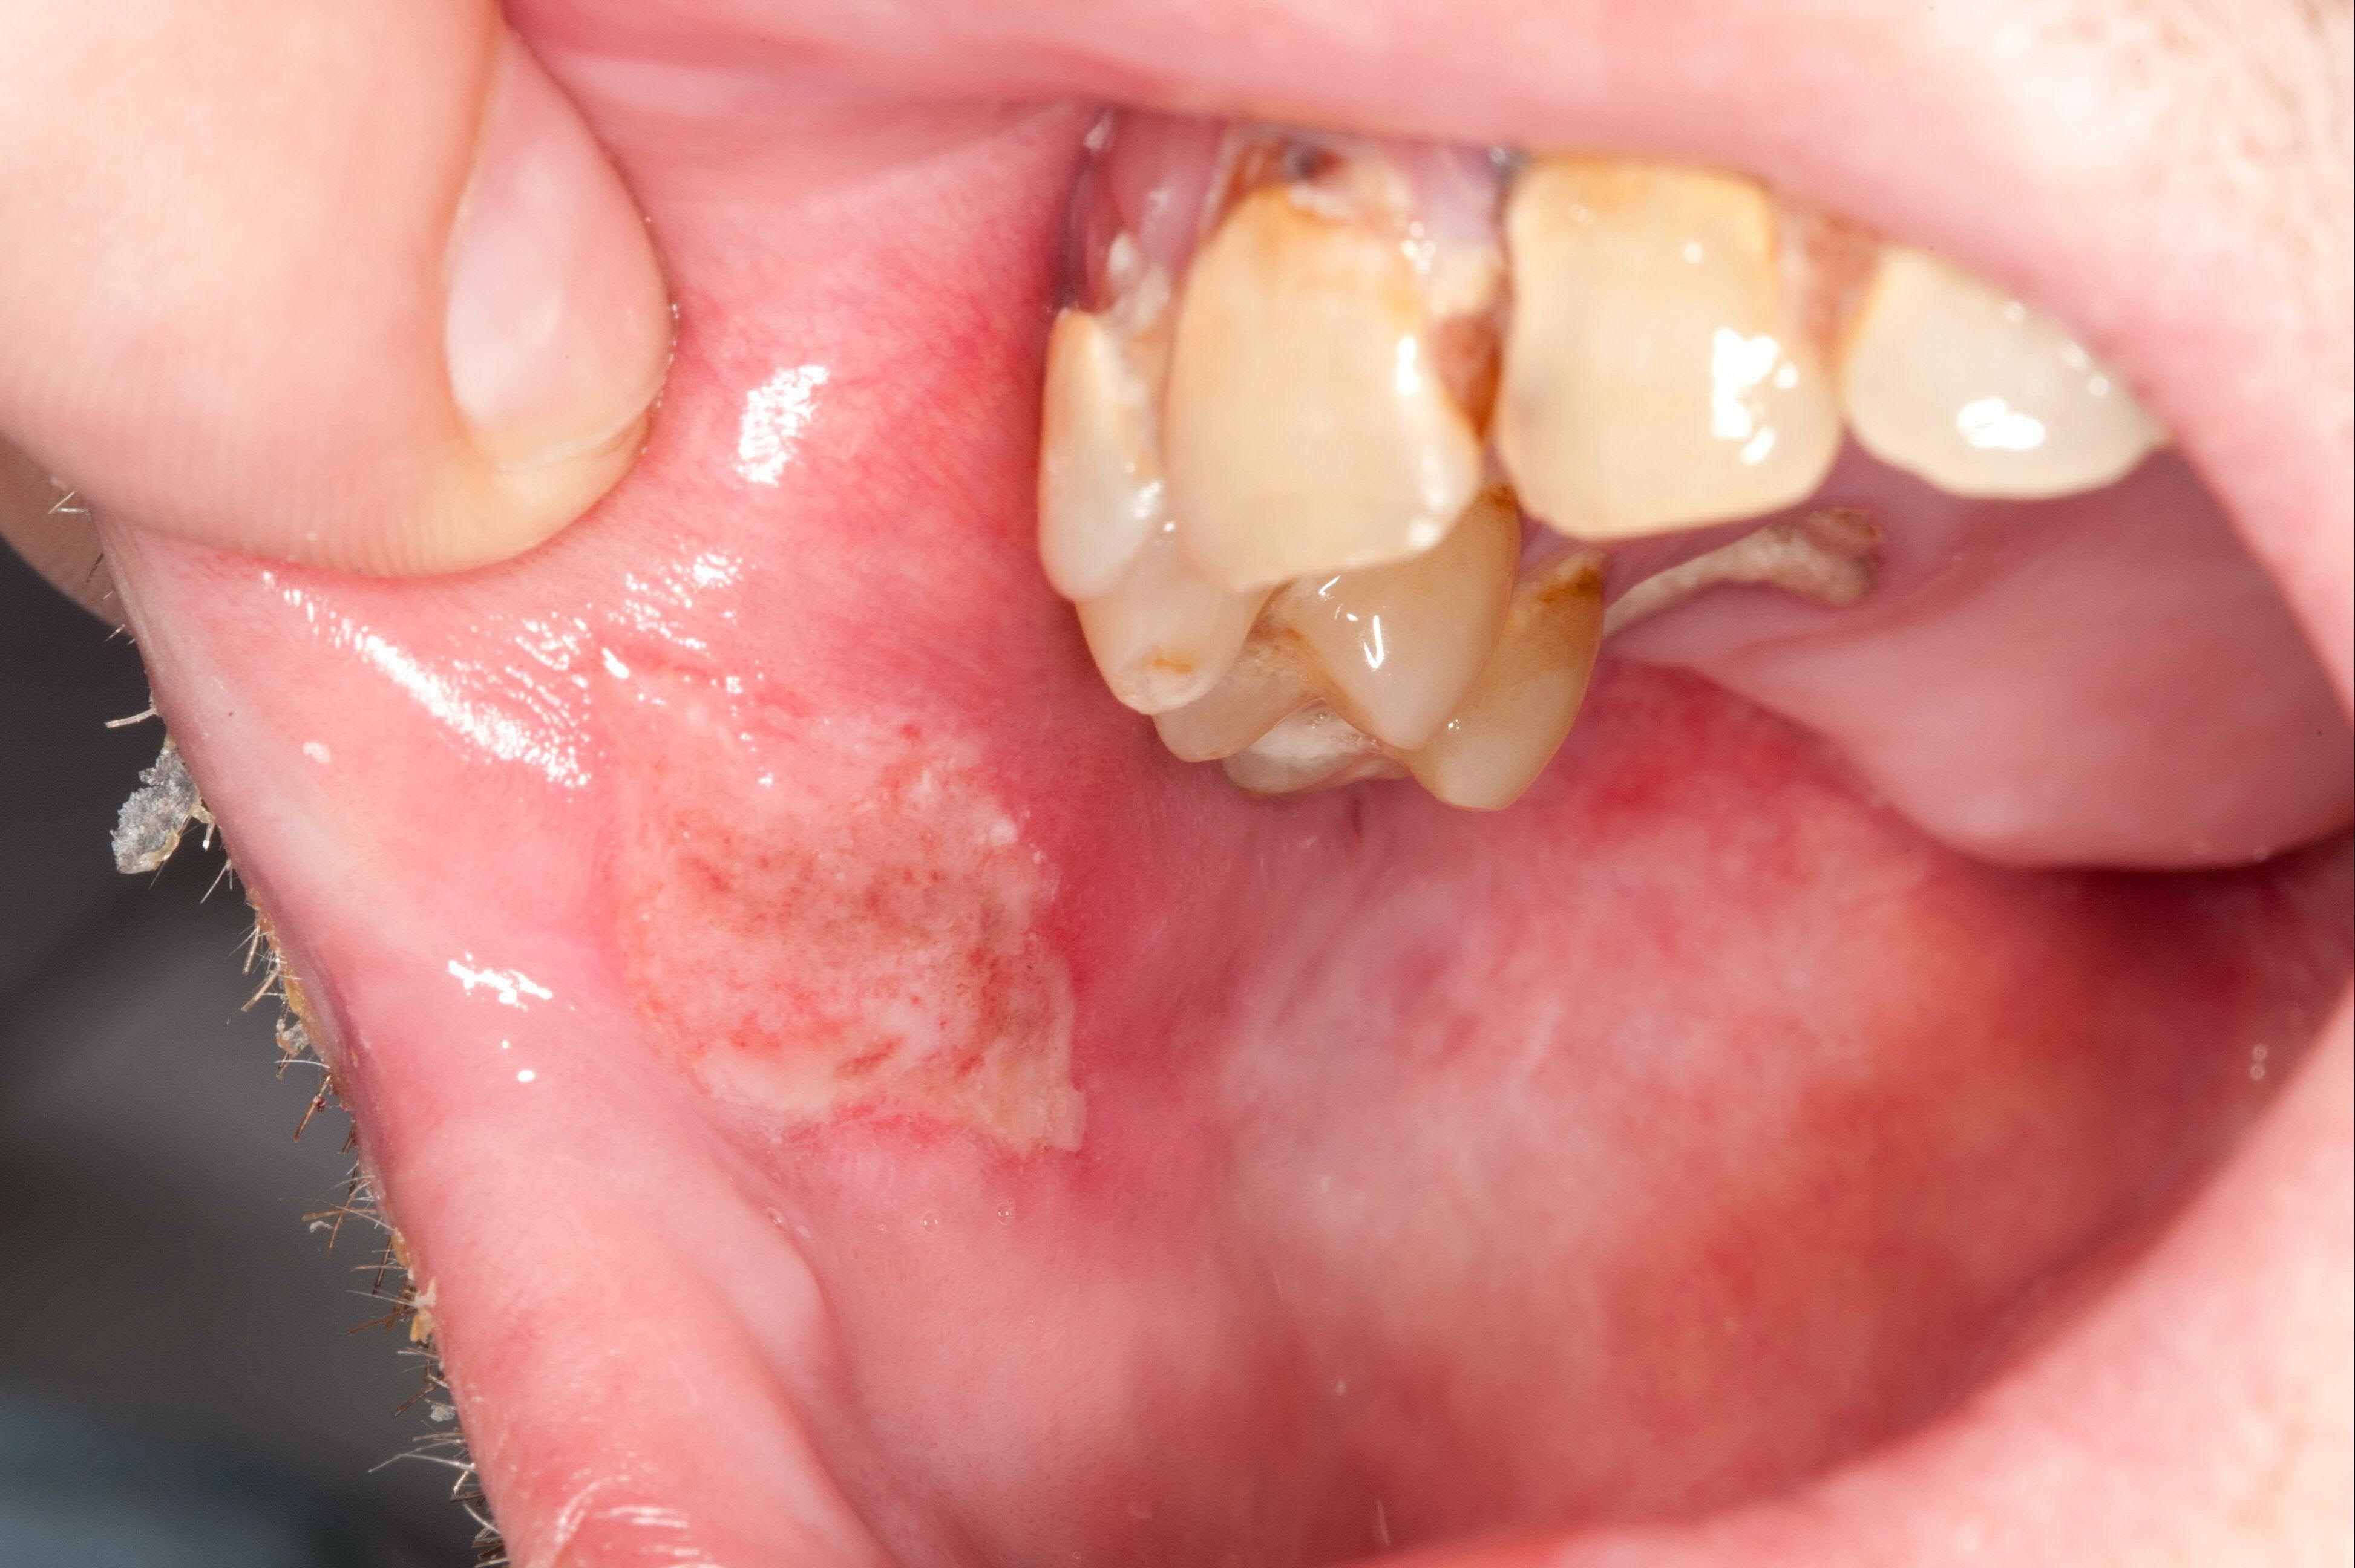

Traumatic ulcer example.

Another traumatic ulcer example, often from ongoing irritation (teeth, appliances).

Common locations

- along cheek bite lines

- tongue edges

- under dentures, braces, or sharp teeth/fillings

Healing time

Typically heals in about 5 to 10 days once the source of irritation is removed.